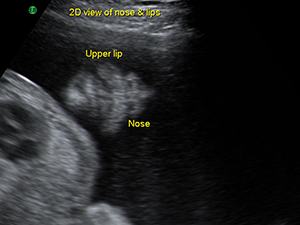

中孕期的鼻子與咀唇